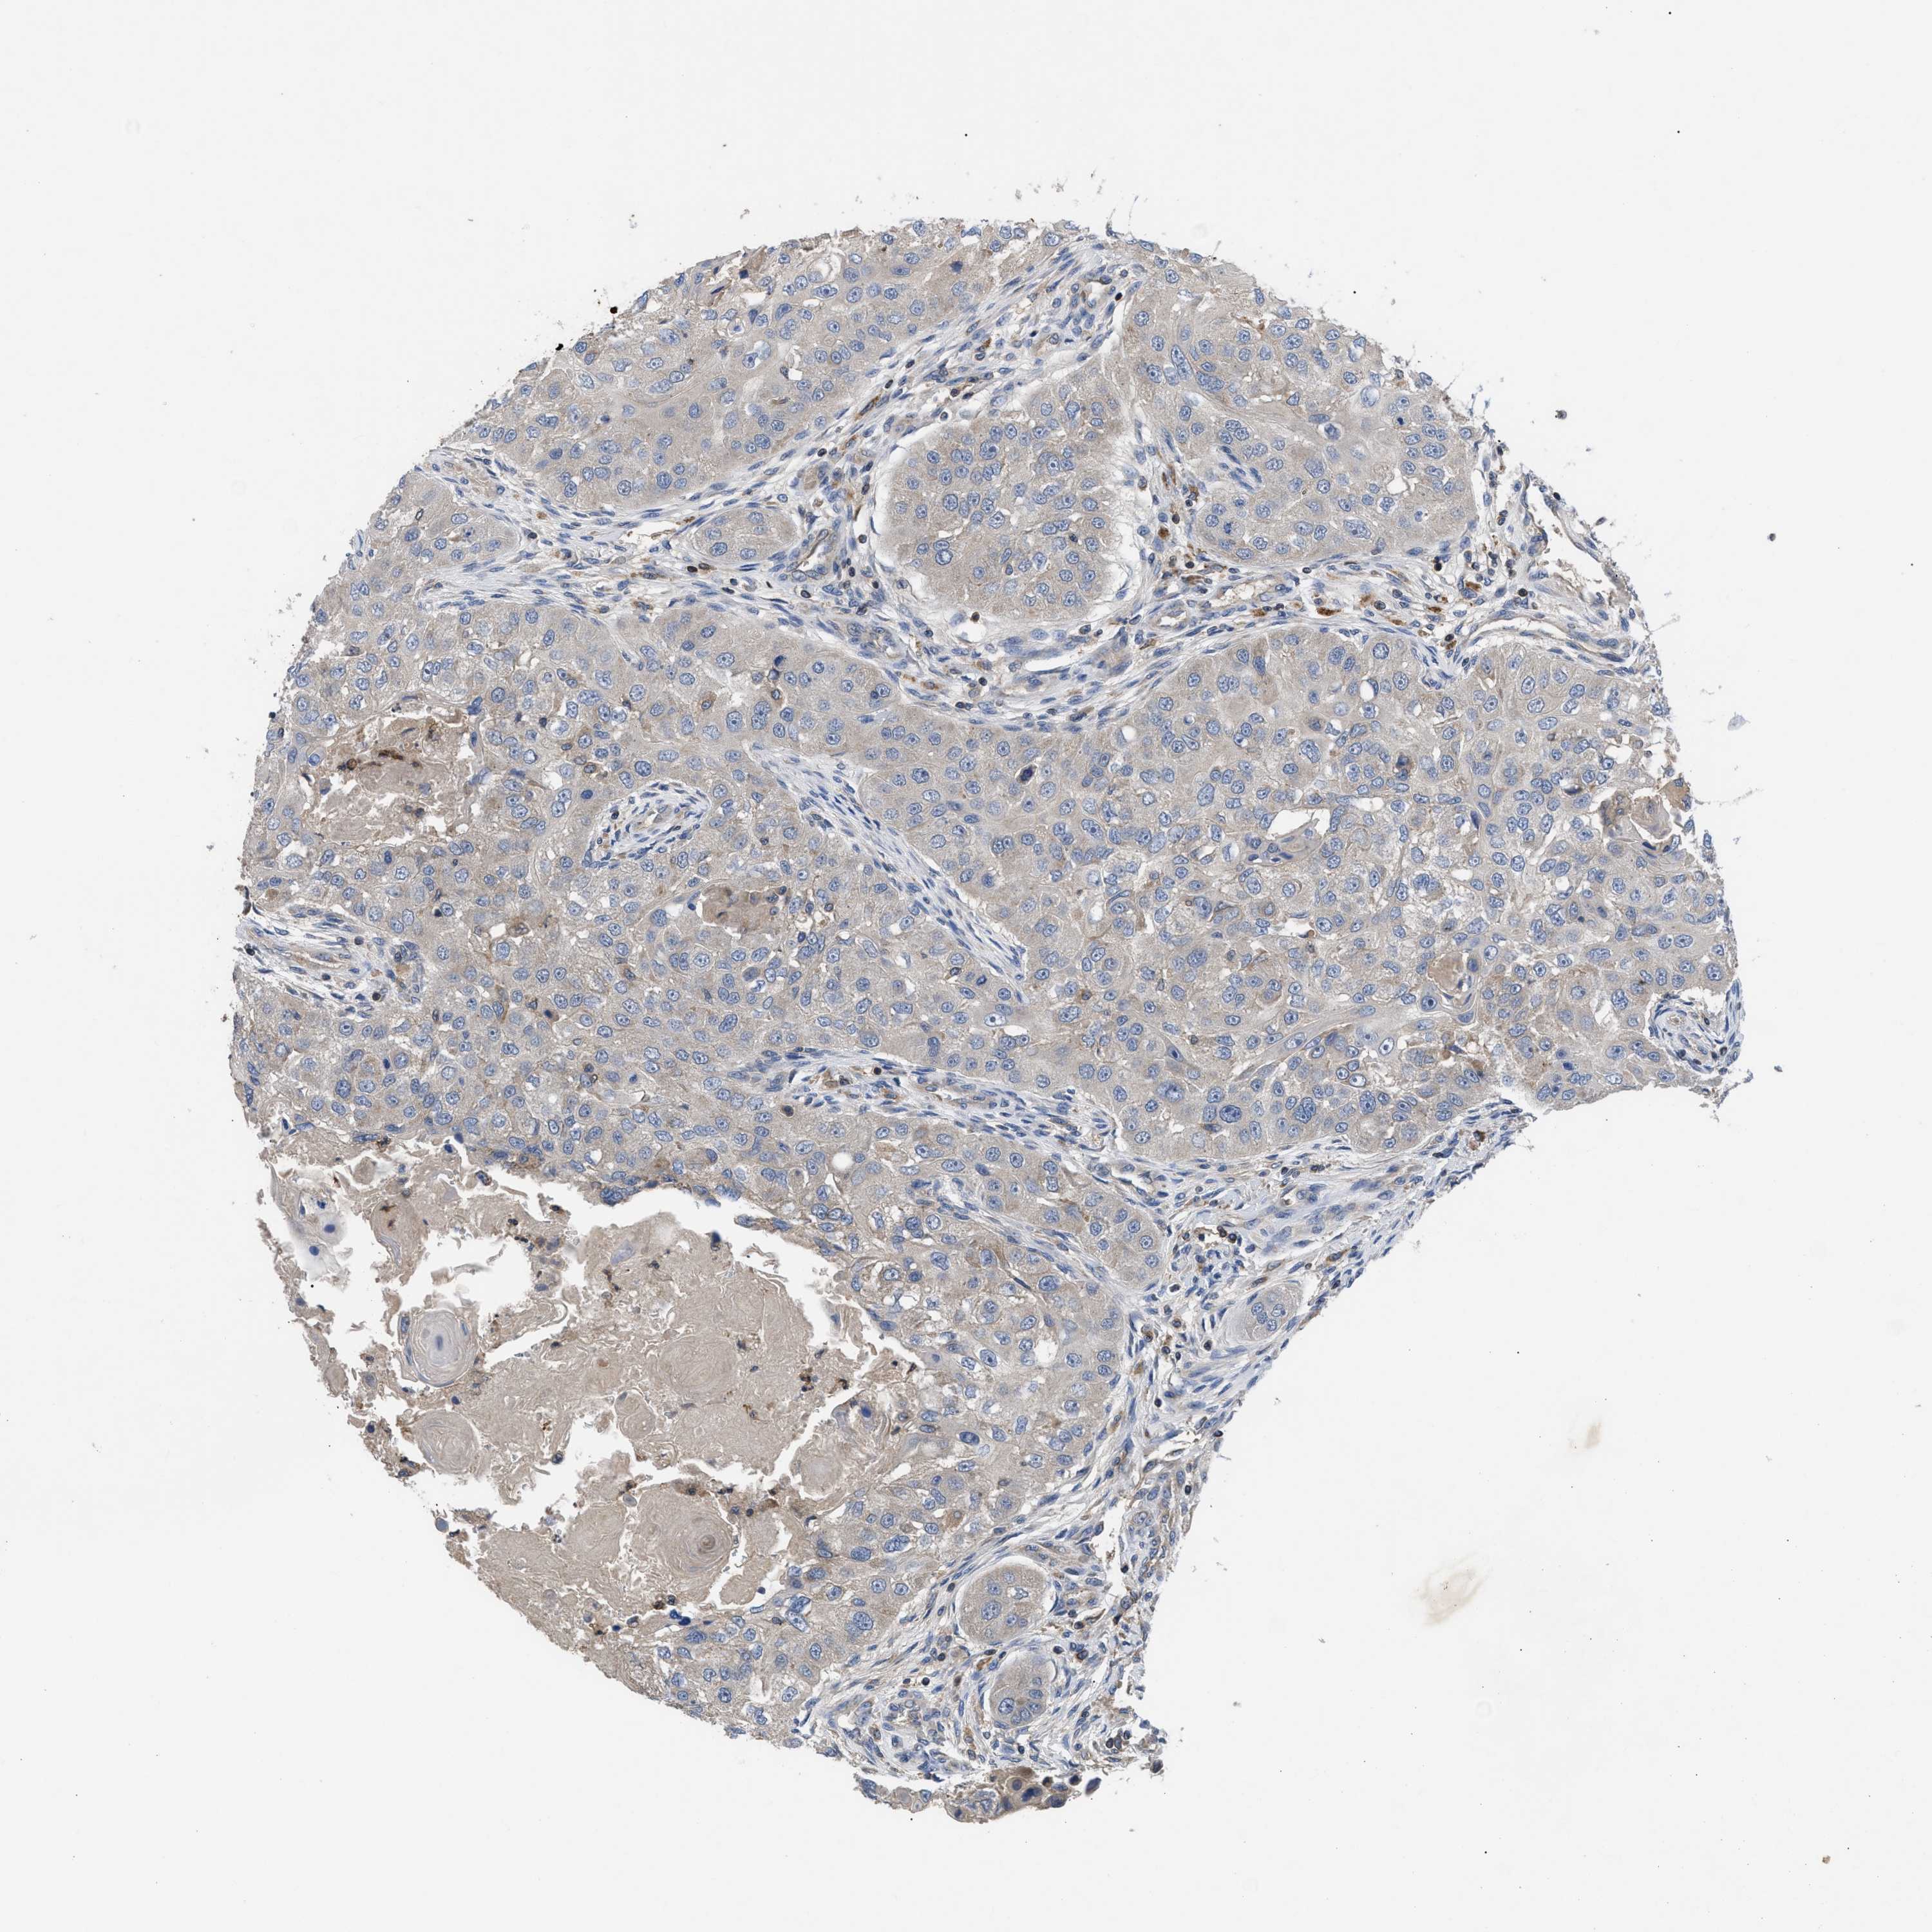

HEAD AND NECK CANCER - Protein expressioni

A mouse-over function shows sample information and annotation data. Click on an image to view it in a full screen mode. Samples can be filtered based on level of antibody staining by selecting one or several of the following categories: high, medium, low and not detected. The assay and annotation is described here.

Antibody stainingi

Antibody staining in the annotated cell types in the current human tissue is reported as not detected, low, medium, or high, based on conventional immunohistochemistry profiling in selected tissues. This score is based on the combination of the staining intensity and fraction of stained cells.

Each image is clickable and will lead to virtual microscopy that enables deeper exploration of all samples and also displays staining intensity scores, fraction scores and subcellular localization as well as patient and tissue information for each sample.

Antibody HPA018162

Staining

High

Medium

Low

Not detected

Intensity

Strong

Moderate

Weak

Negative

Quantity

>75%

75%-25%

<25%

None

Location

Nuclear

Cytoplasmic/membranous

Cytoplasmic/membranous,nuclear

Squamous cell carcinoma, NOS

Squamous cell carcinoma, metastatic, NOS

Adenocarcinoma, NOS